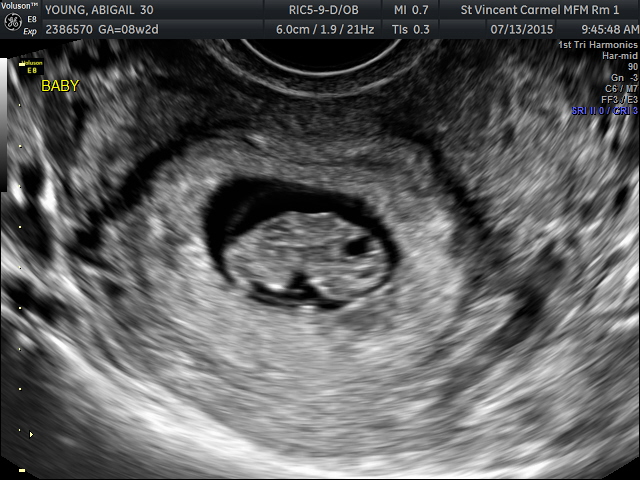

Had my first ultrasound today at 9w+6 it was pretty amazing to finally see! We couldn't hear the heartbeat but we could see it flickering and watched bubs tiny little arms wave too. The ultrasound just makes it look like a blurry jellybean!